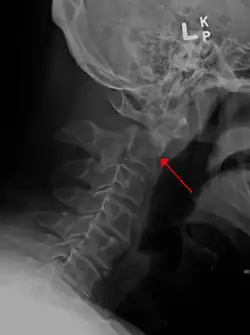

Detección radiográfica

En la tomografía computarizada o en la radiografía, puede visualizarse directamente una fractura cervical. Además, los signos indirectos de lesión de la columna vertebral son las incongruencias de las líneas cervicales, y/o el aumento del grosor del espacio prevertebral.[1]